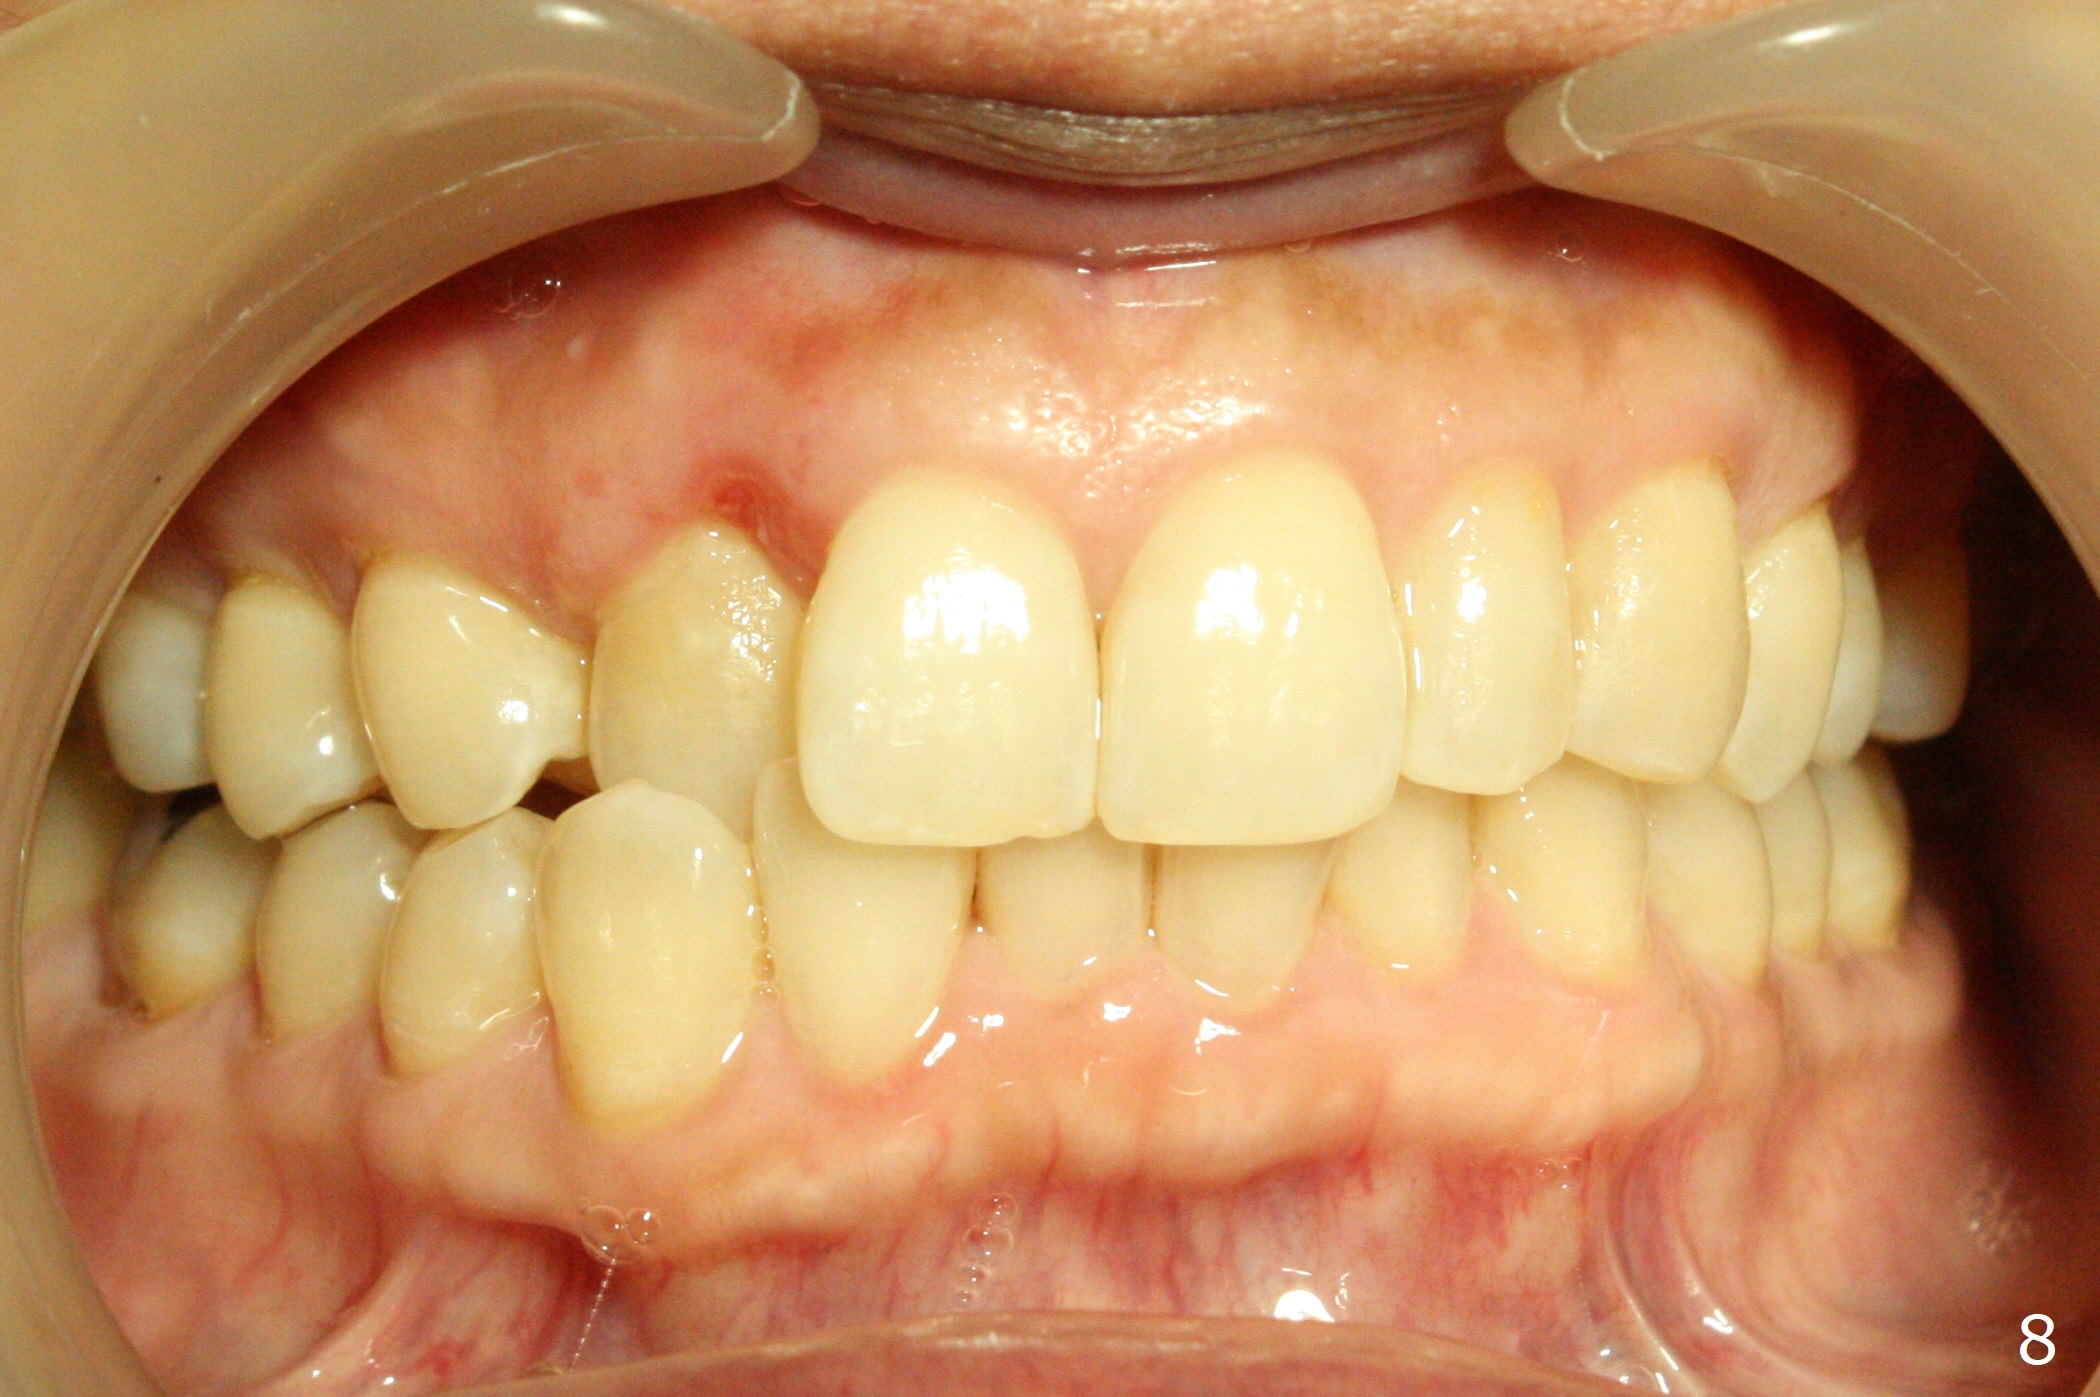

A 54-year-old woman (dento-phobic) will return for banding and bracketing 1.5 months post UR2 extraction with socket preser-vation. Lip strain is absent or minimal(Fig.1). The upper dental midline deviates to the right (Fig.2). Profile is within normal limit (Fig.3). UR3 is in cross bite (Fig.4). Cephalmetric X-ray apparently shows normal profile (Fig.5). Occlusion appears to be Class II in canine and molar (Fig.7,9, Class II Division II Malocclusion). The upper and lower dental midlines mismatch (Fig.8). UL2 is a peg lateral (Fig.10), while the lower anteriors are crowded (Fig.11). Arch wire sequence is conducted and let the timid patient decide whether the 2nd part of treatment should restore ideal occlusion with UR2 implant and UL2 veneer or simply close diastemata. Take PAs for the anteriors prior to banding to follow up root resorption during treatment.